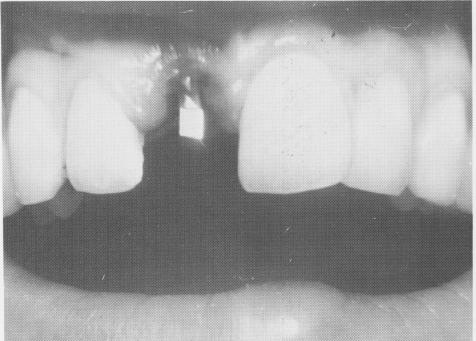

In this case a maxillary right central incisor lost in an accident 3 years previously was to be replaced with a single tooth implant (Fig. 8-22). The patient, a young, attractive girl in her late twenties, had been wearing a removable acrylic denture that held the missing tooth. An alginate impression of both arches and an accurate wax bite were taken. From the articulated casts, a prefabricated single tooth restoration of porcelain-baked-to-metal was processed (Fig. 8-23). Lingually, it contained two rests that fitted firmly against the lingual aspects of both neighboring teeth (Fig. 8-24). These rests prevented the tongue from pushing out the tooth labially. On the labial aspect, in order to prevent the tooth from being pushed lingually, the junction of the distolabioproximal line angle and the mesiolabioproximal line angle was fashioned to slightly overlap labially the same surfaces of the two teeth that flanked it on both sides (Fig. 8-25).

Fig. 8-25. The labial view of the restoration.